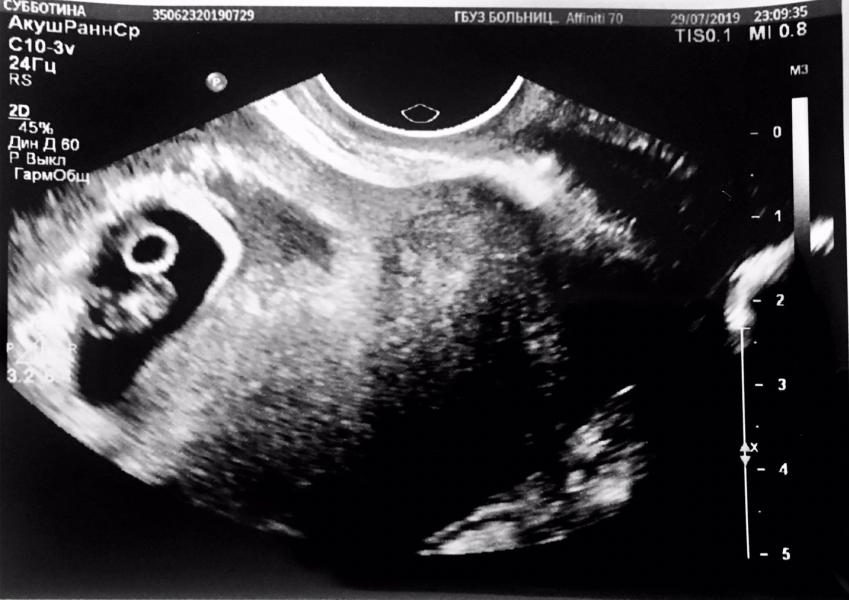

Ну вот и пришёл долгожданный день ))) сделали узи - ходили с мужем )))

Имеется 1 живой плод, и гематома которая уже как бы рассасывается , вроде ничего страшного , но назначили «или /или» Дюфастон или Утрожестан 200.

Срок совпадает с менструальным сроком , сегодня ровно 7 недель по срокам и размерам .